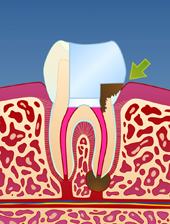

En rotfylt tann er ofte svekket på grunn av store fyllinger og lite gjenværende tannsubstans (fig. I). Som resultat vil en rotfylt tann være mer utsatt for å knekke enn en tann som ikke er rotfylt (fig. II-III). Dersom rotfyllingen blir utsatt for lekkasje over lengre tid, kan bakterier komme til og lage en ny infeksjon i den rotfylte tannen (fig. IV). Der er derfor viktig å kontakte tannlege snarest dersom deler av en rotfylt tann knekker av.

| figur I | | figur II | | figur III | | figur IV |

På samme måte kan et dypt hull i tannen medføre at bakterier kommer

inn til rotfyllingen og infiserer denne på ny (fig. V-VIII). Det er

derfor svært viktig med grundig renhold, også rundt rotfylte tenner.

| figur V | | figur VI | | figur VII | | figur VIII |